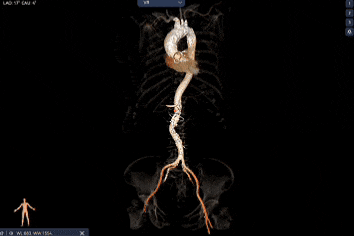

外周双侧入路无明显迂曲、直径可容纳20F大鞘通过,双侧中分叉,穿刺需注意。主动脉弓角弓距可,髂总动脉及分支多处钙化,瓷化升主动脉,钙化由升主动脉蔓延至主动脉弓侧壁及弓顶弓底部,有一定卒中和夹层风险。

经过庄晓东教授团队分析,拟右股动脉作为主入路,使用可调弯长鞘建立通道,使用18mm球囊预扩,选择AV23号Prostyle A®瓣膜进行释放。

Step 1.升主动脉情况评估